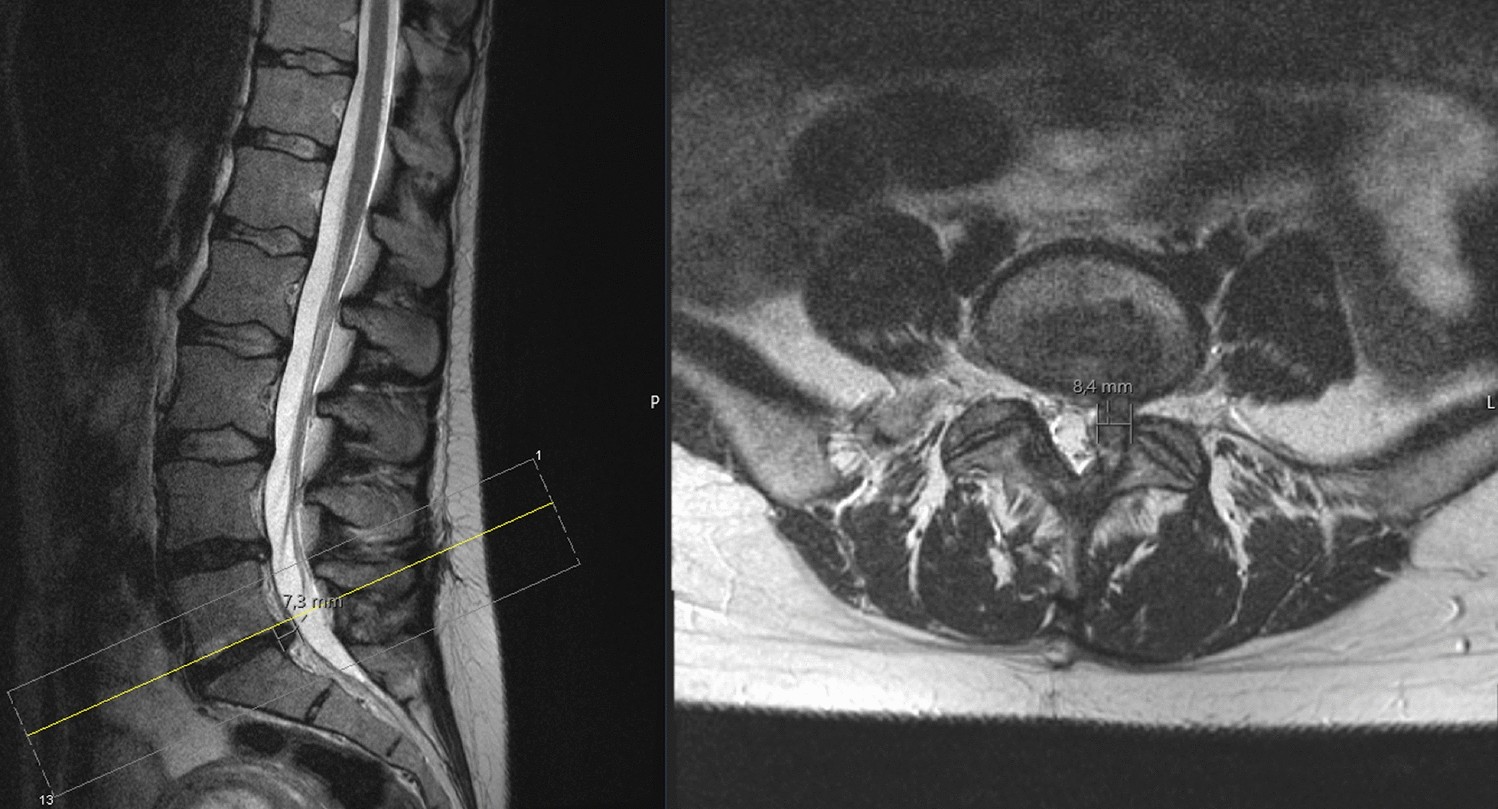

MR imaging of the lumbar spine with sagittal (left) and axial (right) sequencing showing a disk prolapse at the level L5/S1 on the left side